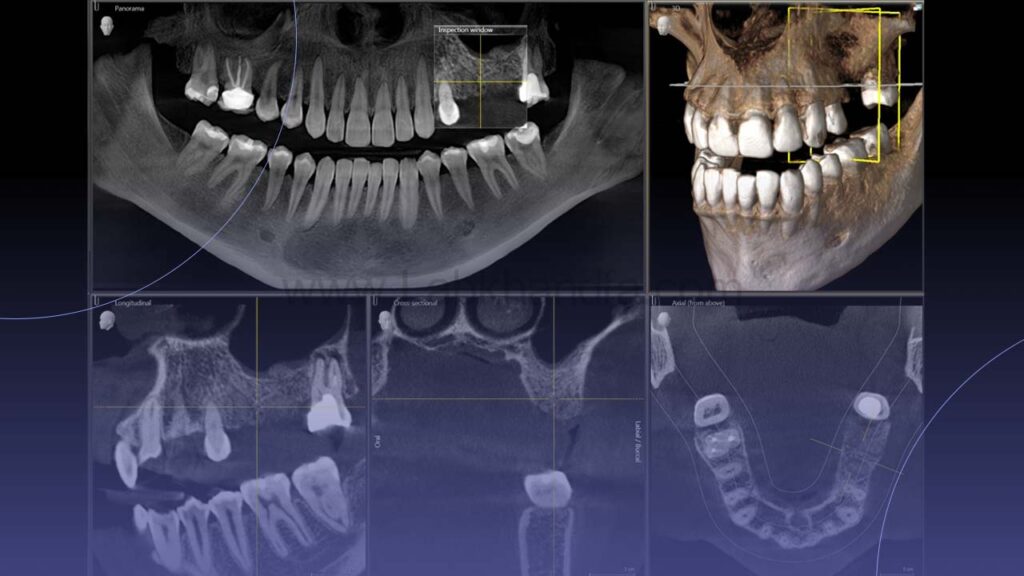

3. عکسبرداری و تهیه قالب

برای برنامه ریزی دقیق، از فک و دندان ها عکس رادیوگرافی تهیه می شود. در برخی موارد نیز از دهان قالب گیری می شود تا مدل سه بعدی از دندان ها به دست آید. این تصاویر و مدل ها برای طراحی طرح درمان ضروری هستند.